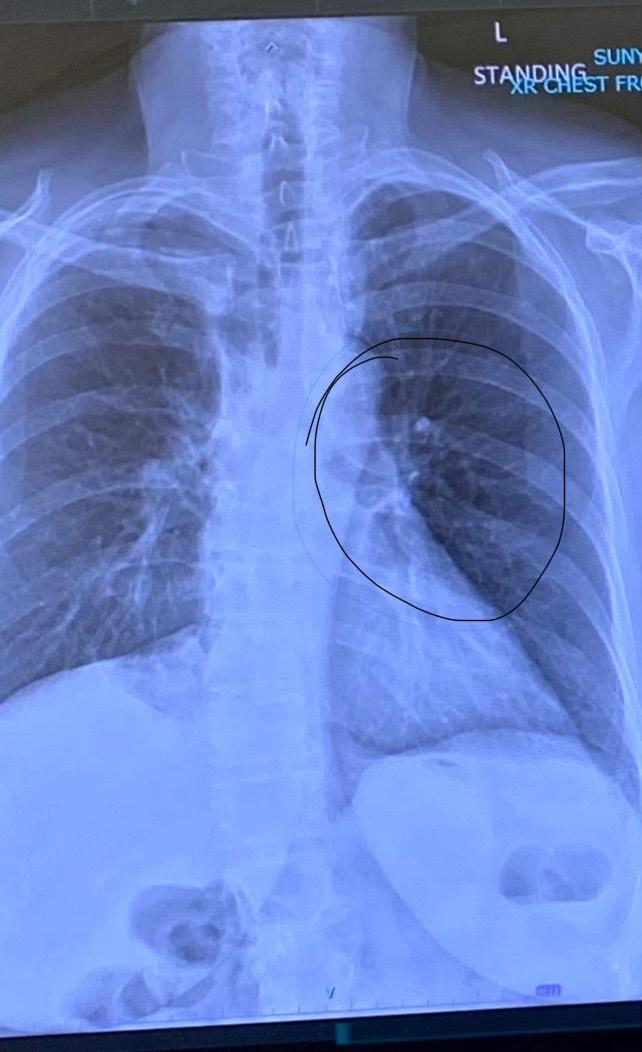

The screening showed a spot on her right lung. She followed up with a PET scan, a biopsy and a CT with contrast scan. She was diagnosed with non-small cell cancer, which makes up 80% to 85% of all lung cancers, according to the American Cancer Society.

She said she opted for surgery instead of doing chemo first. In February, she underwent surgery and had the top half of her right lung removed. During the surgery, doctors

found a second spot.